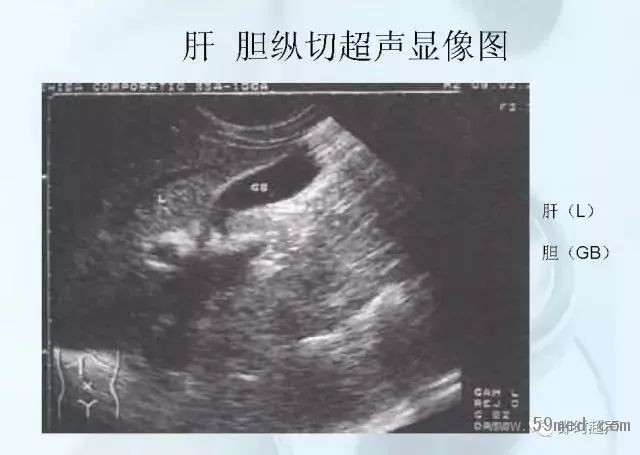

新聞中心 收藏!正常B超解剖圖譜,超實用!